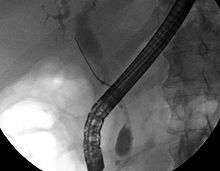

While abdominal imaging can be useful in the diagnosis of cholangiocarcinoma, direct imaging of the bile ducts is often necessary. Endoscopic retrograde cholangiopancreatography (ERCP), an endoscopic procedure performed by a gastroenterologist or specially trained surgeon, has been widely used for this purpose. Although ERCP is an invasive procedure with attendant risks, its advantages include the ability to obtain biopsies and to place stents or perform other interventions to relieve biliary obstruction.[7] Endoscopic ultrasound can also be performed at the time of ERCP and may increase the accuracy of the biopsy and yield information on lymph node invasion and operability.[47] As an alternative to ERCP, percutaneous transhepatic cholangiography (PTC) may be utilized. Magnetic resonance cholangiopancreatography (MRCP) is a non-invasive alternative to ERCP.[48][49][50] Some authors have suggested that MRCP should supplant ERCP in the diagnosis of biliary cancers, as it may more accurately define the tumor and avoids the risks of ERCP.[51][52][53]